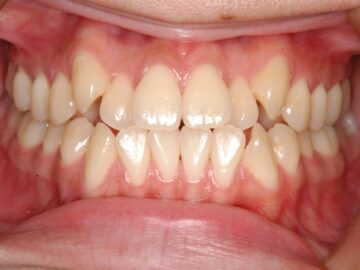

治療後

歯ぐきが薄く口唇がわずかに突出しているため、小臼歯抜歯での治療を勧めた。

| 抜歯部位 | 上顎左右測第一小臼歯、下顎左右測第一小臼歯 |

動的治療期間 1年7か月、保定治療期間 1年10か月 |

合計925,100円:消費税10%込(税抜841,000円) 内訳(税込):精密検査診断料77,000円、初回オーラルケア16,500円、矯正料572,000円(クリアタイプブラケット)、調節料6,600円×18回、観察料3,300円×6回、保定処置料110,000円、リテーナー料11,000円 |